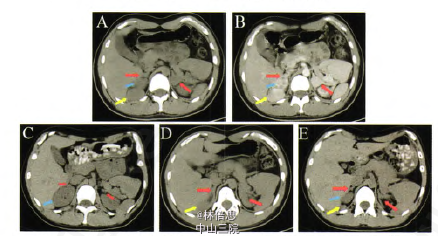

患者,男性,21岁,“生长发育提前5年,色素沉着伴性格渐变10年”。实验室检查:血皮质醇8:00为37.I o.g/L、16:00为27.9g/L、24:00为12.6斗g/L[正常参考范围67~226(8:00),下同],24 h尿皮质醇39.38斗∥24 h(21一111),ACTH 990.81pg/ml(12.00—78),血醛固酮430.76 p∥ml(38.1~313.3),血浆肾素活性8.5l ng·ml一·h。1(O.73,17.4),LH<0.07 IU/L(1.1—8.8),FSH 0.03 IU/L(0.9~12.0),孕酮9.39ng/ml(<0.1~0.2),睾酮4.61 rig/ml(1.66—8.11),硫酸脱氢表雄酮355.40¨s/dl(136.2~591.9),17一羟孕酮>50.00 ng/ml(0.5—2.4),雄烯二酮>10.00 rig/ml(0.30~2.63)。GnRH兴奋试验示LH、FSH均不能被激发。基因测序示该患者CYP21A2基因复合杂合改变($268T,Q318X)。精液分析:排精量0.6 ml(>2),pH 7.4(7.2~8.0),活动率26.14%(>60%),精子密度3.47x106/ml(≥20x106)。性腺B超示双侧睾丸约30 mmxl5 mmx20 mm,实质内皆可见大小不等实质不均质回声团块,左侧大者23 mmXl7 mm。右侧大者20 mmxl3mln,边界尚清,形态不规则,内可见散在沙粒样强回声点。结合病史考虑睾丸肾上腺残余肿瘤。肾上腺CT平扫+增强示双侧 。肾上腺明显结节状增粗,右侧肝肾隐窝处可见一占位,大小约2.5 cmxl.2 cm。CT定位下右侧肝肾隐窝病灶穿刺活检病理示肾上腺皮质增生。诊断明确后给予醋酸地塞米松0.75 mg每日一次口服。皮肤色素沉着较前减轻。体力、精神较前好转.性格逐渐开朗。血皮质醇0.14 Ixg/L, ACTHl4.84pg/ml,17一羟孕酮2.39 ng/ml,雄烯二酮0.87 ng/ml。睾丸B超示左右侧睾丸大小均约35 mmX 16 mmx27 mm,双侧睾丸实质内可见大小不等低回声,左侧大者16 mmx9 mm.右侧大者16 mmx8 mm:肾上腺CT平扫示双侧肾上腺增生较前明显减轻,肝肾隐窝病灶明显缩小.肾脏上移。精液分析:排精量0.6 ml,pH 7.7,精子活动率50.4%,精子密度50.4 X 106/ml。 讨论:H是一组因肾上腺皮质激素合成途径中酶缺陷引起的疾病,属常染色体隐性遗传病。21.羟化酶是肾上腺类固醇激素合成的关键酶之一,由CPY21A2编码,21一OHD与CYP21基因突变 有关,可使糖皮质激素和(或)盐皮质激素合成减少,引起前体物质17一羟孕酮和孕酮堆积,并向雄激素合成途径分流,导致雄烯二酮和T异常升高。同时,皮质醇的合成减少,将会引起ACTH反馈性升高。临床较常见的为女性男性化,需要结合基因筛查以明确诊断。常有家族史。此类患者由于长期高水平ACTH,使肾上腺易发生腺瘤样增生。因此,,治疗的过程中需根据血皮质醇、ACTH、17-羟孕酮的变化调整剂量,其中血浆ACTH水平恢复正常是说明激素替代治疗合适的最重要的实验 室指标。对于CAH合并l肾上腺肿块患者,需行穿刺病理活检明确肿块性质,更加要避免因为肿大的肾上腺而进行没有必要的手术。